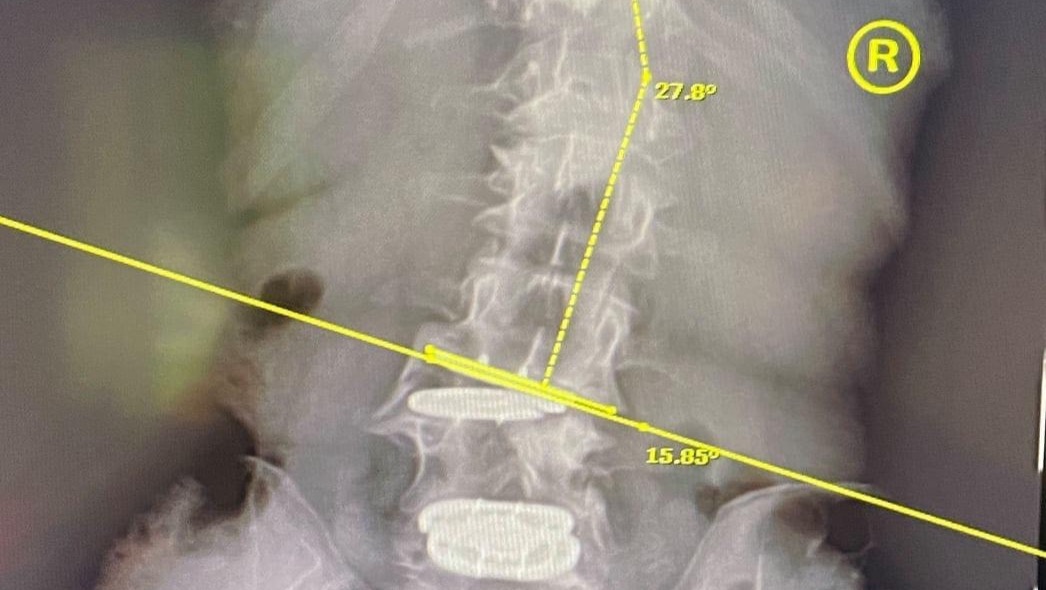

This is an X-ray of an image of my Lumbar Spine with the failed medical devices (Artificial discs at the Lumbar L3/L4 & L4/L5 Levels):

On the second day after the surgery, I began experiencing excruciating pain. My lower back implant (2 Level ADR M6 Lumbar Implant) was malfunctioning as indicated by X-rays, however, I was told it was only due to swelling and muscle weakness. No admittance of the surgery being a failure, no admittance of the implant being defective.